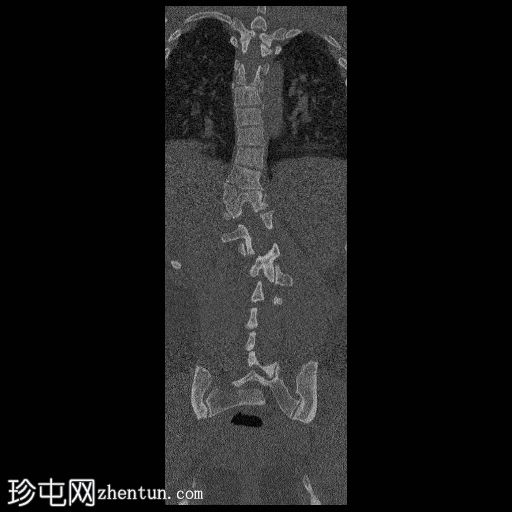

CT

冠状位骨窗

胸腰段交界处可见右侧完全节段性半椎体(轴位/矢状位/冠状位)。

未见与上方或下方相邻椎体融合的迹象。